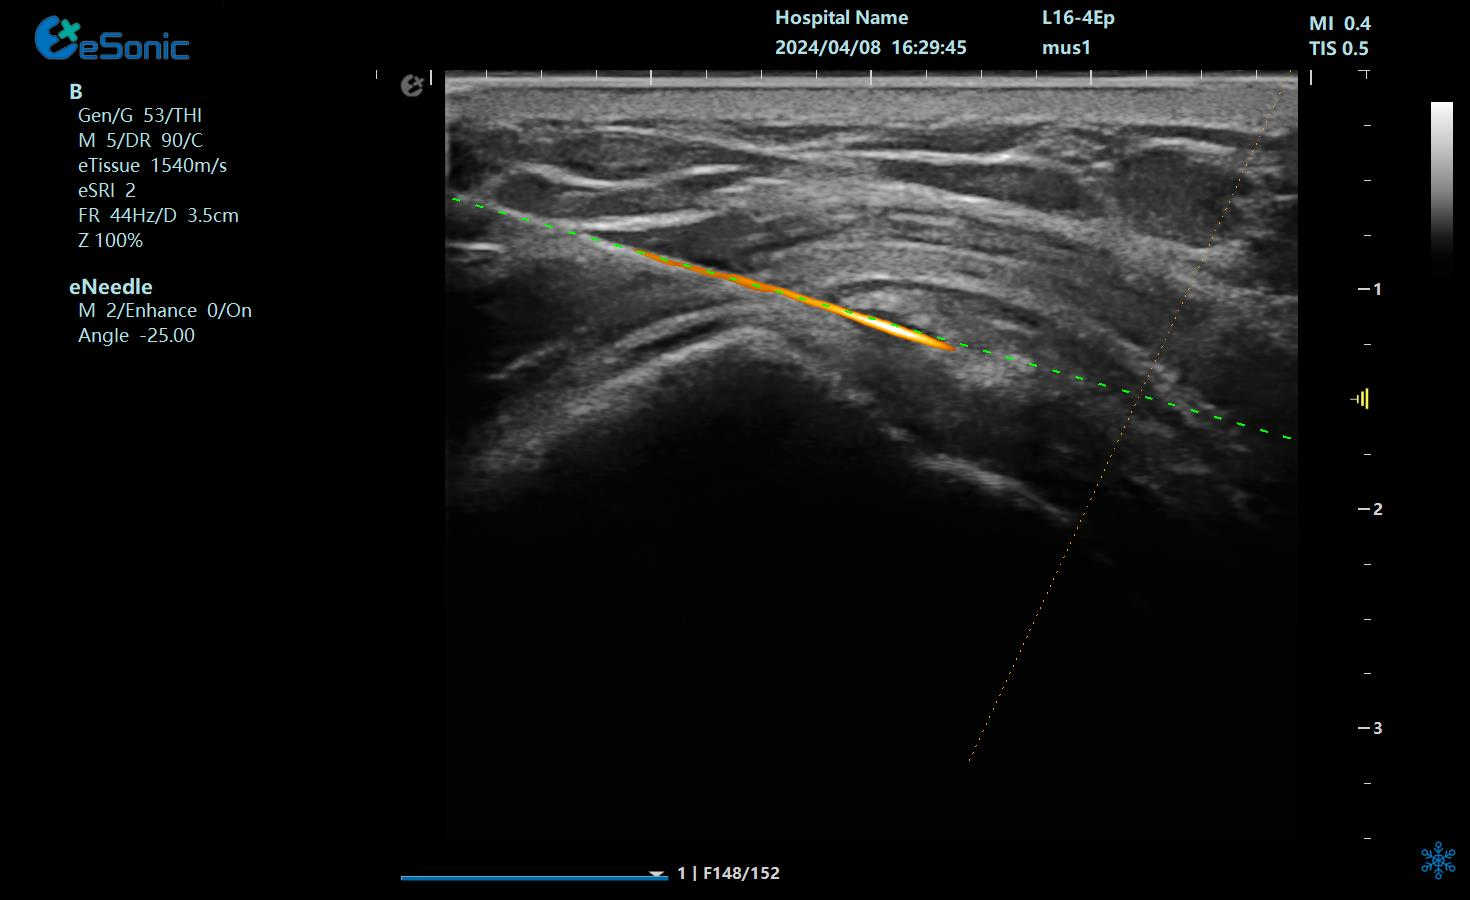

治疗中使用穿刺针智能Map和无磁导航技术

在与钙化性肌腱炎的斗争中,精准是胜利的关键。利来国国际网站医疗的“Needle TsTM”技术凭借其智能Map技术和无磁导航系统,成功解决了传统超声引导穿刺中的难题,让针尖与钙化灶清晰可辨。这种创新不仅提高了手术的成功率,更减少了患者的痛苦和恢复时间。如今,我们不再需要担心手术中的不确定性和风险,因为“Needle TsTM”为我们提供了前所未有的精准保障。它让那些曾经困扰我们的“小石头”无处遁形,让康复之路变得更加顺畅。